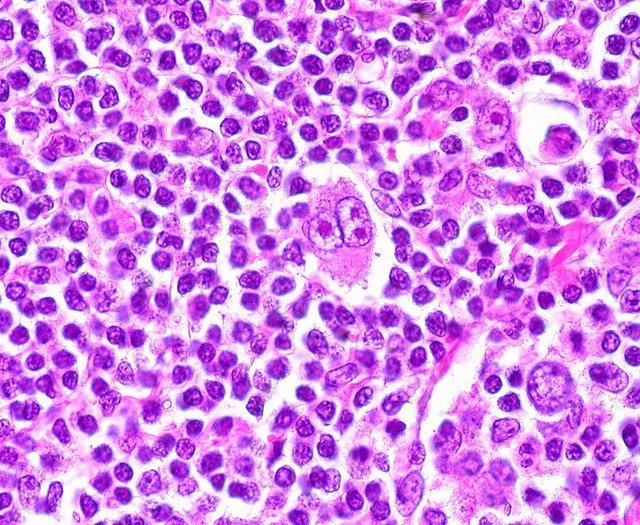

Linfoma di Hodgkin: cos'è, cause, diagnosi, trattamento, sopravvivenza e cura di questo tumore del sistema linfatico. Il linfoma di Hodgkin è un tipo di linfoma, un tumore del sistema linfatico. Si origina dai linfociti B, un tipo di globuli bianchi che svolgono un ruolo importante nel sistema immunitario, ed ècaratterizzato dalla presenza.. Prognosi e stadiazione La Prognosi. Con il termine di prognosi si intende la possibilità di prevedere l'evoluzione della malattia in un preciso soggetto in termini di guaribilità, di sopravvivenza (che ad oggi si aggira intorno al 80% per i Linfomi di Hodgkin e al 60% per i Linfomi Non Hodgkin) e di qualità di vita.Come per ogni malattia tumorale, anche nel caso dei linfomi, la prognosi.